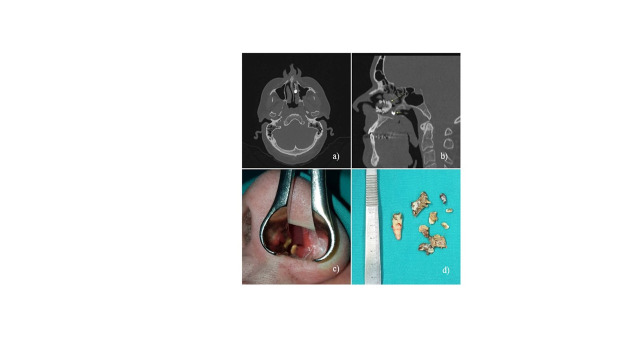

鼻腔内出现超常齿(SNT)是一种罕见情况,文献资料有限。我们报告了两例有鼻塞和呼吸困难病史的病例。在这两个病例中,临床和放射学检查都证实了鼻腔内的 SNT。在全身麻醉的情况下,使用罗彻斯特-潘氏器械经鼻进行了摘除术。此外,还对鼻内 SNT 进行了文献综述。通过数据库搜索,共检索到 1970 年至 2020 年期间的 50 个病例。患者的平均年龄为 22.5 岁。最常见的症状是单侧呼吸受阻和头痛。建议通过手术取出鼻内 SNT 以消除症状。

The presence of supernumerary tooth (SNT) in the nasal cavity is a rare condition with limited literature data. We report two cases with a history of nasal obstruction and difficulty breathing. In both cases, clinical and radiological examination confirmed intranasal SNT. Extractions were executed in general anesthesia using Rochester-Pean instruments transnasally. In addition, a literature review of intranasal SNT was performed. The database search retrieved a total number of 50 cases in time period from 1970 to 2020. Mean age of patients was 22.5 years. Most common symptoms were unilateral obstruction of breathing and headache. Surgical extraction of intranasal SNT is recommended to eliminate the symptoms.